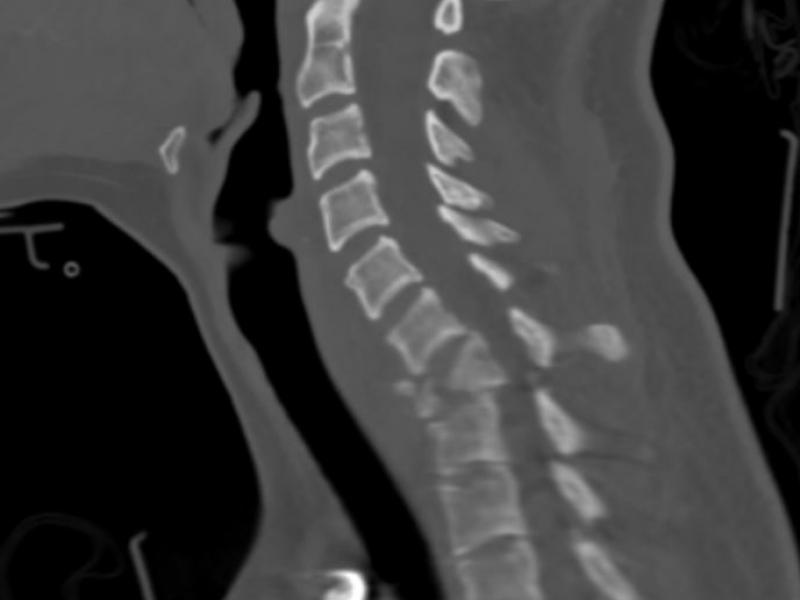

A 20 yo F presents to the ED following a restrained driver